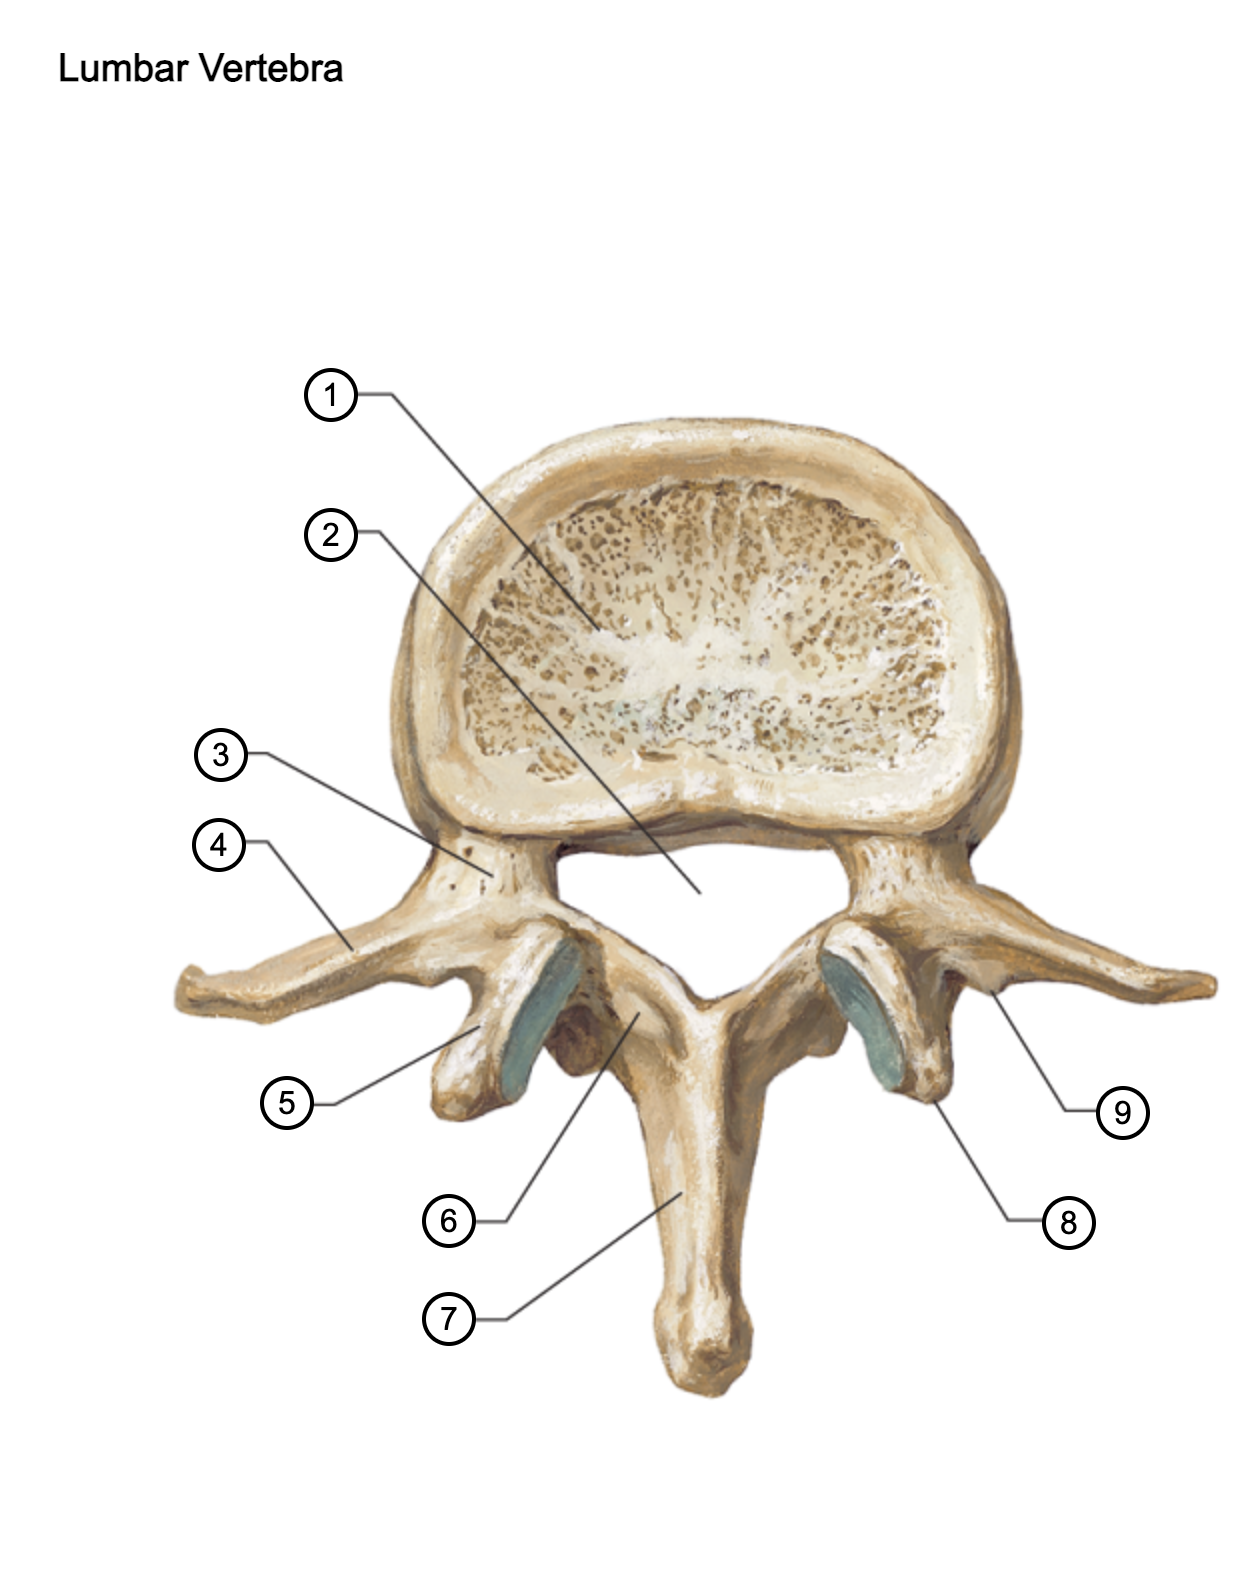

1

vertebral body

2

vertebral foramen

3

pedicle

4

transverse process

5

superior articular process

6

lamina

7

spinous process

8

mammillary process

9

accessory process